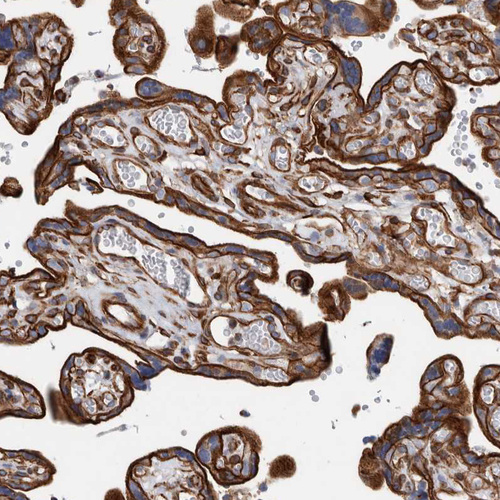

Immunohistochemistry analysis in human skeletal muscle and liver tissues using HPA025967 antibody. Corresponding PLEC RNA-seq data are presented for the same tissues.